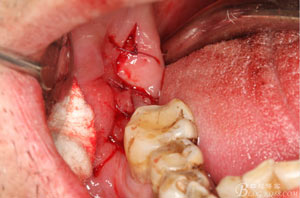

圖6.行角形瓣切開、翻瓣、暴露骨面,可見48牙冠表面有炎性肉芽組織

圖7.高速牙鉆去骨。逐漸可見48的牙冠

圖8.刮除牙冠表面的肉芽組織后,可見48 的牙冠